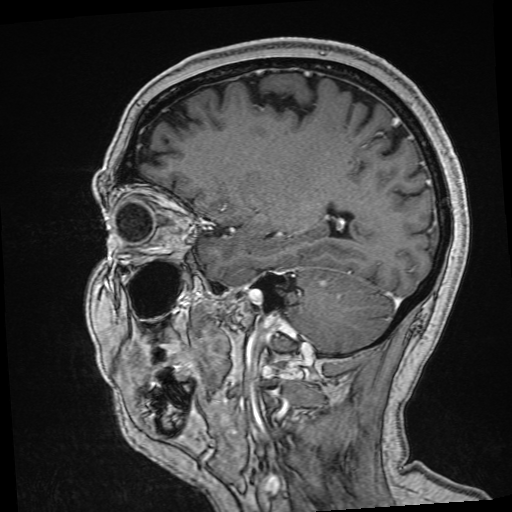

Refer to captionRefer to caption𝐱PCsubscript𝐱PC\mathbf{x}_{\mathrm{PC}}bold_x start_POSTSUBSCRIPT roman_PC end_POSTSUBSCRIPTRefer to captionRefer to caption𝐱LDsubscript𝐱LD\mathbf{x}_{\mathrm{LD}}bold_x start_POSTSUBSCRIPT roman_LD end_POSTSUBSCRIPTRefer to captionRefer to caption𝐱SDsubscript𝐱SD\mathbf{x}_{\mathrm{SD}}bold_x start_POSTSUBSCRIPT roman_SD end_POSTSUBSCRIPTRefer to captionRefer to captionAm-3D [14]Refer to captionRefer to captionPa-2.5D [8]Refer to captionRefer to caption𝐱^SDsubscript^𝐱SD\hat{\mathbf{x}}_{\mathrm{SD}}over^ start_ARG bold_x end_ARG start_POSTSUBSCRIPT roman_SD end_POSTSUBSCRIPT (ours)Refer to captionRefer to caption𝐱PCsubscript𝐱PC\mathbf{x}_{\mathrm{PC}}bold_x start_POSTSUBSCRIPT roman_PC end_POSTSUBSCRIPTRefer to captionRefer to caption𝐱LDsubscript𝐱LD\mathbf{x}_{\mathrm{LD}}bold_x start_POSTSUBSCRIPT roman_LD end_POSTSUBSCRIPTRefer to captionRefer to caption𝐱SDsubscript𝐱SD\mathbf{x}_{\mathrm{SD}}bold_x start_POSTSUBSCRIPT roman_SD end_POSTSUBSCRIPTRefer to captionRefer to captionAm-3D [14]Refer to captionRefer to captionPa-2.5D [8]Refer to captionRefer to caption𝐱^SDsubscript^𝐱SD\hat{\mathbf{x}}_{\mathrm{SD}}over^ start_ARG bold_x end_ARG start_POSTSUBSCRIPT roman_SD end_POSTSUBSCRIPT (ours)Refer to captionRefer to caption𝐱PCsubscript𝐱PC\mathbf{x}_{\mathrm{PC}}bold_x start_POSTSUBSCRIPT roman_PC end_POSTSUBSCRIPTRefer to captionRefer to caption𝐱LDsubscript𝐱LD\mathbf{x}_{\mathrm{LD}}bold_x start_POSTSUBSCRIPT roman_LD end_POSTSUBSCRIPTRefer to captionRefer to caption𝐱SDsubscript𝐱SD\mathbf{x}_{\mathrm{SD}}bold_x start_POSTSUBSCRIPT roman_SD end_POSTSUBSCRIPTRefer to captionRefer to captionAm-3D [14]Refer to captionRefer to captionPa-2.5D [8]Refer to captionRefer to caption𝐱^SDsubscript^𝐱SD\hat{\mathbf{x}}_{\mathrm{SD}}over^ start_ARG bold_x end_ARG start_POSTSUBSCRIPT roman_SD end_POSTSUBSCRIPT (ours)Refer to captionRefer to caption𝐱PCsubscript𝐱PC\mathbf{x}_{\mathrm{PC}}bold_x start_POSTSUBSCRIPT roman_PC end_POSTSUBSCRIPTRefer to captionRefer to caption𝐱LDsubscript𝐱LD\mathbf{x}_{\mathrm{LD}}bold_x start_POSTSUBSCRIPT roman_LD end_POSTSUBSCRIPTRefer to captionRefer to caption𝐱SDsubscript𝐱SD\mathbf{x}_{\mathrm{SD}}bold_x start_POSTSUBSCRIPT roman_SD end_POSTSUBSCRIPTRefer to captionRefer to captionAm-3D [14]Refer to captionRefer to captionPa-2.5D [8]Refer to captionRefer to caption𝐱^SDsubscript^𝐱SD\hat{\mathbf{x}}_{\mathrm{SD}}over^ start_ARG bold_x end_ARG start_POSTSUBSCRIPT roman_SD end_POSTSUBSCRIPT (ours)Refer to captionRefer to caption𝐱PCsubscript𝐱PC\mathbf{x}_{\mathrm{PC}}bold_x start_POSTSUBSCRIPT roman_PC end_POSTSUBSCRIPTRefer to captionRefer to caption𝐱LDsubscript𝐱LD\mathbf{x}_{\mathrm{LD}}bold_x start_POSTSUBSCRIPT roman_LD end_POSTSUBSCRIPTRefer to captionRefer to caption𝐱SDsubscript𝐱SD\mathbf{x}_{\mathrm{SD}}bold_x start_POSTSUBSCRIPT roman_SD end_POSTSUBSCRIPTRefer to captionRefer to captionAm-3D [14]Refer to captionRefer to captionPa-2.5D [8]Refer to captionRefer to caption𝐱^SDsubscript^𝐱SD\hat{\mathbf{x}}_{\mathrm{SD}}over^ start_ARG bold_x end_ARG start_POSTSUBSCRIPT roman_SD end_POSTSUBSCRIPT (ours)Refer to captionRefer to caption𝐱PCsubscript𝐱PC\mathbf{x}_{\mathrm{PC}}bold_x start_POSTSUBSCRIPT roman_PC end_POSTSUBSCRIPTRefer to captionRefer to caption𝐱LDsubscript𝐱LD\mathbf{x}_{\mathrm{LD}}bold_x start_POSTSUBSCRIPT roman_LD end_POSTSUBSCRIPTRefer to captionRefer to caption𝐱SDsubscript𝐱SD\mathbf{x}_{\mathrm{SD}}bold_x start_POSTSUBSCRIPT roman_SD end_POSTSUBSCRIPTRefer to captionRefer to captionAm-3D [14]Refer to captionRefer to captionPa-2.5D [8]Refer to captionRefer to caption𝐱^SDsubscript^𝐱SD\hat{\mathbf{x}}_{\mathrm{SD}}over^ start_ARG bold_x end_ARG start_POSTSUBSCRIPT roman_SD end_POSTSUBSCRIPT (ours)Refer to captionRefer to caption𝐱PCsubscript𝐱PC\mathbf{x}_{\mathrm{PC}}bold_x start_POSTSUBSCRIPT roman_PC end_POSTSUBSCRIPTRefer to captionRefer to caption𝐱LDsubscript𝐱LD\mathbf{x}_{\mathrm{LD}}bold_x start_POSTSUBSCRIPT roman_LD end_POSTSUBSCRIPTRefer to captionRefer to caption𝐱SDsubscript𝐱SD\mathbf{x}_{\mathrm{SD}}bold_x start_POSTSUBSCRIPT roman_SD end_POSTSUBSCRIPTRefer to captionRefer to captionAm-3D [14]Refer to captionRefer to captionPa-2.5D [8]Refer to captionRefer to caption𝐱^SDsubscript^𝐱SD\hat{\mathbf{x}}_{\mathrm{SD}}over^ start_ARG bold_x end_ARG start_POSTSUBSCRIPT roman_SD end_POSTSUBSCRIPT (ours)

Figure 5: Qualitative comparison for test samples of the SLD-METS dataset. The zooms highlight the metastasis location. By design, our approach adds the CE signal to the input image, thereby preserving its image quality. The input images at the top have the same resolution, while they strongly differ at the bottom. Thus, the image quality of our output 𝐱^SDsubscript^𝐱SD\hat{\mathbf{x}}_{\mathrm{SD}}over^ start_ARG bold_x end_ARG start_POSTSUBSCRIPT roman_SD end_POSTSUBSCRIPT is poor in the bottom row and decent in the top row.

The average mean and maximal relative enhancement across the 351351351351 lesions is listed in the c¯¯𝑐\overline{c}over¯ start_ARG italic_c end_ARG and c^^𝑐\widehat{c}over^ start_ARG italic_c end_ARG columns of Table 1. Our approach significantly improves the predicted CE strength compared to Am-3D and Pa-2.5D. Note that c¯¯𝑐\overline{c}over¯ start_ARG italic_c end_ARG is not only sensitive to the CE strength (as c^^𝑐\widehat{c}over^ start_ARG italic_c end_ARG), but also to a lesion’s internal morphology and border delineation. A qualitative comparison of a typical lesion is visualized in the zooms at the top row of Figure 5. While Am-3D struggles to predict the internal morphology of the lesions, the CE strength of Pa-2.5D is too low. In contrast, our approach predicts the right contrast strength, morphology, and boundary of the lesion.